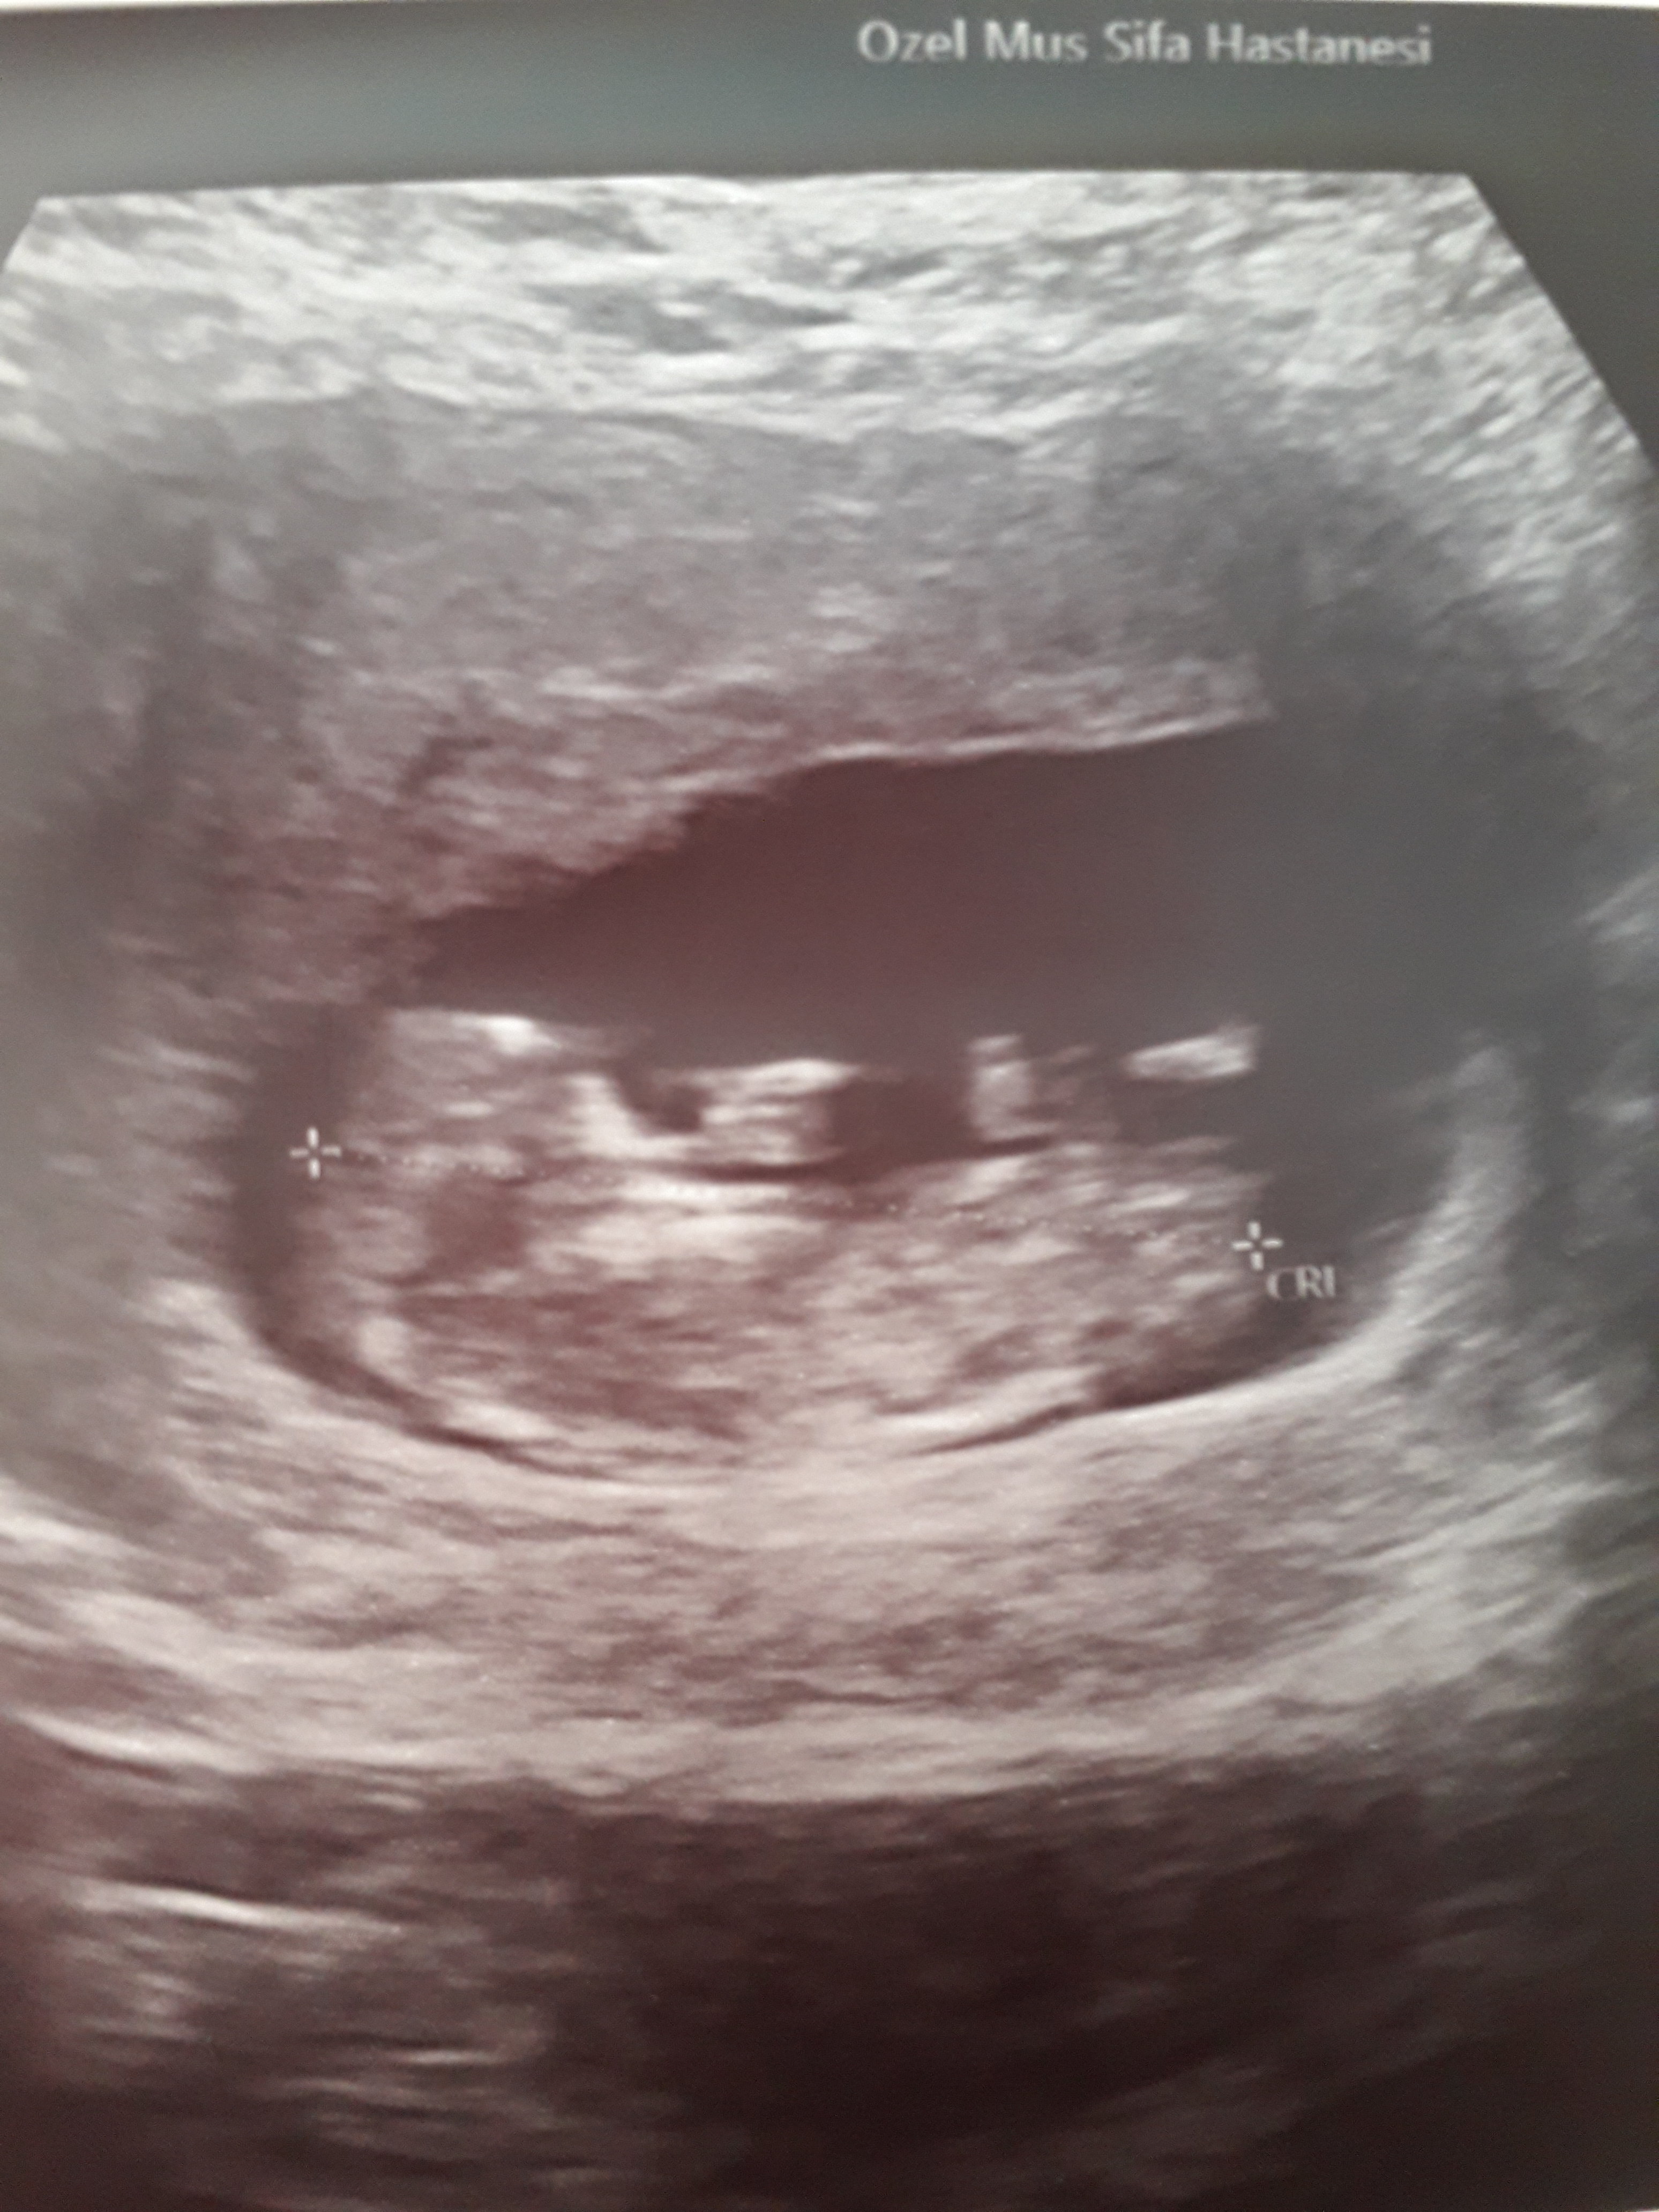

Merhaba ,

Nub teorisiyle cinsiyeti uzman hekimler belirleyebiliyormuş. Bu yüzden doğruluk payı var.

Nub teorisi ile ilgili istatistiki bilgiler şöyledir;

1 hafta sonunda, doğruluk oranı 48 yüzde olduğu

12 hafta sonunda, doğruluk oranı 91 yüzde olduğu

13 hafta sonunda, doğruluk oranı 94 yüzde olduğu